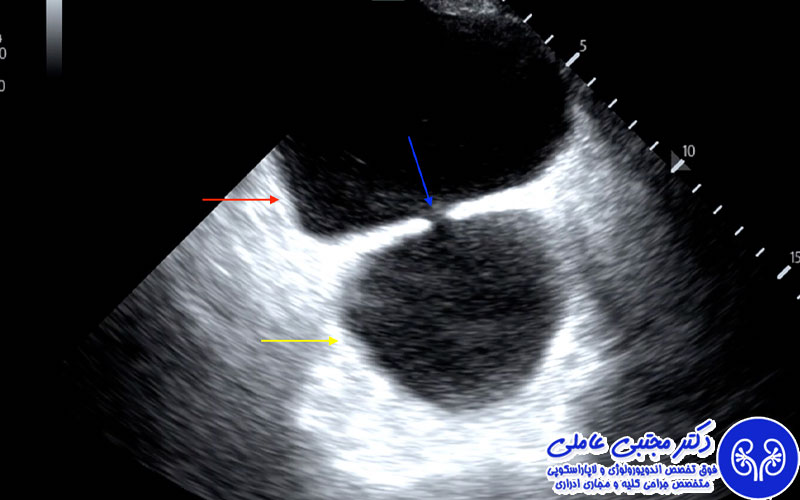

دیورتیکول مثانه عارضه ای است که در دیواره مثانه اتفاق می افتد. دیورتیکول شبیه به حباب یا کیسه ای به نظر می رسد که از دیواره داخلی مثانه بیرون زده است. دیورتیکول مثانه دو نوع کاذب و واقعی دارد. در دیورتیکول واقعی تمامی لایه های تشکیل دهنده دیواره مثانه در کنار هم باعث تشکیل حباب یا کیسه می شوند اما در دیورتیکول کاذب حباب ها تنها بر اثر غشای مخاطی بیرونی تشکیل می شوند.

نحوه درمان دیورتیکول مثانه برای هر بیمار متفاوت است. پزشک متخصص اورولوژی با ارزیابی آزمایشات و عکس برداری ها و بررسی سلامت کلی بیمار، اندازه و نوع دیورتیکول، نوع بیماری های زمینه ای و نوع علائم تعیین می کند که این بیماری با چه روشی درمان شود. در ادامه به برخی از روش های درمان دیورتیکول مثانه اشاره شده است.

زمانی که اندازه دیورتیکول کوچک باشد، علائم خاصی ندارد و در روند دستگاه ادراری اختلال ایجاد نمی کند. در نتیجه پزشک با تجویز دارو و توصیه های لازم درباره تغییر سبک زندگی تلاش می کند تا مانع پیشرفت این بیماری شود. مراجعه منظم به پزشک از مهم ترین کارهایی است که بیماران مبتلا دیورتیکول با وجود نداشتن علائم جدی باید انجام دهند.

در مواردی که دیورتیکول بیش از اندازه بزرگ شده باشد و علائمی مانند عفونت و انسداد مجاری ادراری را به همراه داشته باشد، پزشک طی یک جراحی به روش لاپاراسکوپی یا سیستوسکوپی اقدام به برداشتن آن از روی مثانه می کند. گاهی اندازه دیورتیکول و محل قرارگیری آن به گونه ای است که متخصص اورولوژی ناچار می شود برای برداشتن آن عمل جراحی باز انجام دهد.